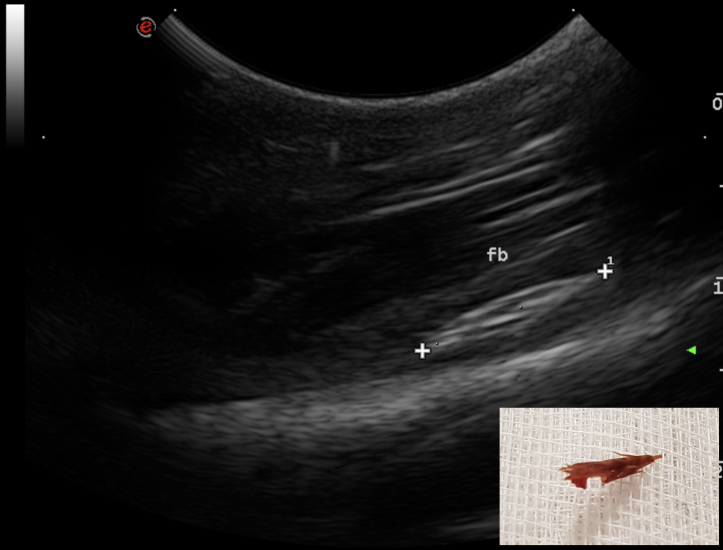

The use of ultrasound for the detection of such foreign bodies is well known and their ultrasonographic features have been widely discussed. Grass awns ‘appear as linear spindle-shaped hyperechoic structures of variable length, with two or three parallel reflecting interfaces corresponding to the seeds and seed covers. Often an anechoic halo due to the accumulation of fluid is present around the foreign body, which sometimes improves interface visualisation’.

Four dogs referred for recurrent abscess in the lumbar region have been seen at the hospital between October 2018 to January 2019. A migrating vegetal foreign body was identified in each dog with the use of ultrasonography. All retrieval procedures were performed in the sonography suite with the patient under general anaesthesia. The region of interest was aseptically prepared and a small stab incision with a #11 scalpel was performed approx. 2 cm cranial to the foreign body, with the plant awn imaged in sagittal section. A Hartmann forceps was inserted through the skin incision and directed toward the tip of the foreign body under ultrasonographic guidance. The forceps were opened and the foreign body grasped and withdrawn. The shape of the foreign body was compared with the sonographic images and the site of the abscess was re-scanned to determine potential residual foreign bodies or fragments. In all dogs, the abscess was flushed with saline and oral antibiotic therapy was administered for 7–10 days. The duration of the procedure ranged from 20 to 40 minutes. Suture of the skin incision was not necessary.